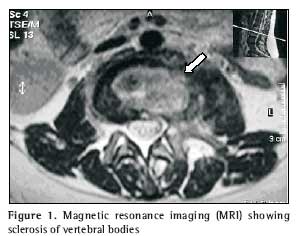

As her condition worsened, leading to difficulty in moving about, she was advised to seek medical assistance at a neurosurgery outpatient clinic, where she was submitted to lumbosacral spine computed tomography, magnetic resonance imaging, chest X-ray, biopsy of the affected site and blood count (including determination of erythrocyte sedimentation rate). Computed tomography revealed irregularity and reduction of the articular space between L2 and L3, concomitant with sclerosis of the corresponding vertebral bodies, as well as fracture in L2. The vertebral disk between L5 and S1 presented a slight protrusion, without causing significant intrarachidian repercussions. The findings suggested the possibility of an inflammatory or infectious process, or both, involving the L2 and L3 vertebral bodies, as well as the corresponding intersomatic disk (Figure 1). Magnetic resonance revealed reduction of the L2/L3 disk space and cold abscess in the corresponding area, which reinforced the possibility of a spondylodiscitis-like process (Figures 2 and 3).